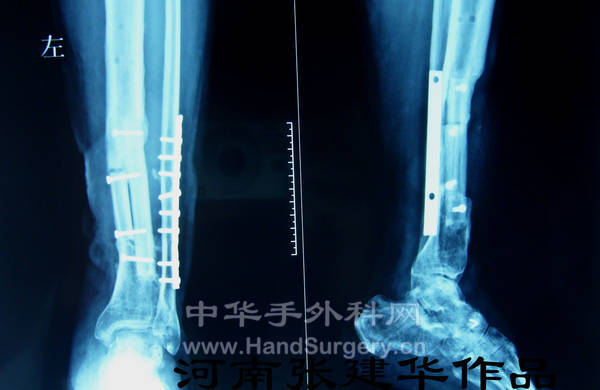

术后X光片

术后半年X光片,骨折愈合良好,去除外固定架,负重活动。